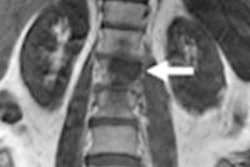

A 15-year-old male patient with osteosarcoma of the left tibia showed good histologic response after completing neoadjuvant chemotherapy. Although the patient was classified as a poor responder based on SUV change, he was classified as a good responder based on ADC change or the combination of SUV change and ADC change. Baseline transverse PET/CT image (A) shows increased FDG uptake of tumor with SUVmax of 2.9. Postchemotherapy PET/CT image (C) shows residual FDG uptake with SUVmax of 2.0, for an SUV change of -31%. In the baseline ADC map (B), mean ADC of tumor was 1.092 x 10-3 mm2/sec. In the postchemotherapy ADC map (D), mean ADC was 1.612 x 10-3 mm2/sec, for an ADC change of 47.6%. Images courtesy of JNM.After the completion of neoadjuvant chemotherapy, all patients had tumors that demonstrated FDG uptake greater than adjacent normal bone. The mean SUVmax of the 27 patients decreased from 9.2 (± 6.0) to 5.4 (± 3.5), while the median ADC value increased from 1.346 × 10-3 mm2/sec to 1.612 × 10-3 mm2/sec after neoadjuvant chemotherapy.